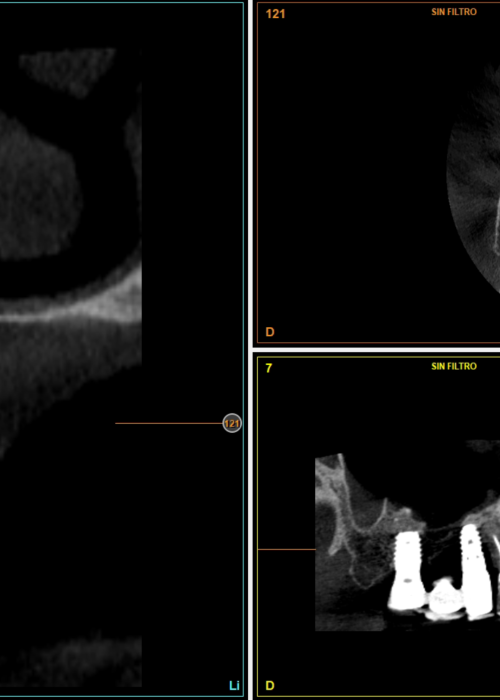

Explantación de implante mal posicionado en sector estético y regeneración posterior con injerto en bloque

Implantes de 4,5 y 5,5 mm longitud insertados de forma directa en elevación crestal con hueso autólogo unido al Endoret-PRGF en alturas óseas residuales de 2-3 mm: estudio retrospectivo